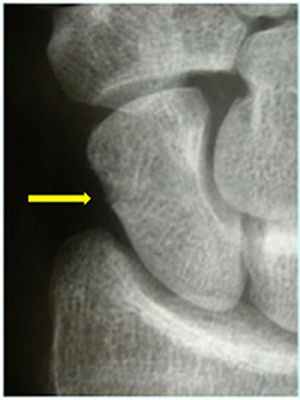

Диагностика: Иногда довольно сложно определить перелом ладьевидной кости. Обычный рентгеновский снимок может не показать перелом ладьевидной кости (рис. 2). При наличии симптомов и отрицательном результате рентгенографии применяются специальные виды исследований при локтевом отведении кисти. Если симптомы указывают на перелом ладьевидной кости, но он не подтверждается рентгеновскими снимками, то рекомендуется иммобилизация и повторный рентген спустя 10-14 дней. Если инструментальная диагностика не дала чёткого ответа проводится компьютерная томография или МРТ.

Foto 2

Foto 3